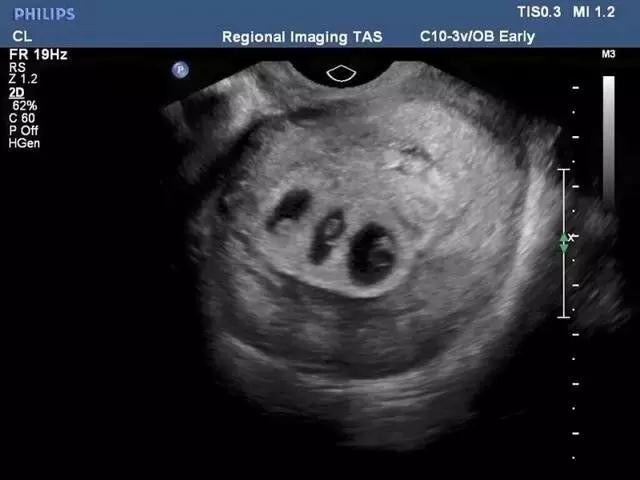

可令他们又惊又喜的是,是个三胞胎,并且真的有个女宝宝。可女宝宝却很弱小,如果继续生存,会很困难。医生建议他们要么减胎(女宝),要么剖腹早产。显然减胎会让另外两个宝宝更加安全,可他们最想要的就是那个女宝,当然三个宝宝都健康出生最好。于是,夫妇二人最后决定冒巨大风险,选择相信自己的三个孩子,相信他们能够健康、坚强的成长。还好,他们有惊无险地度过了整个孕期。